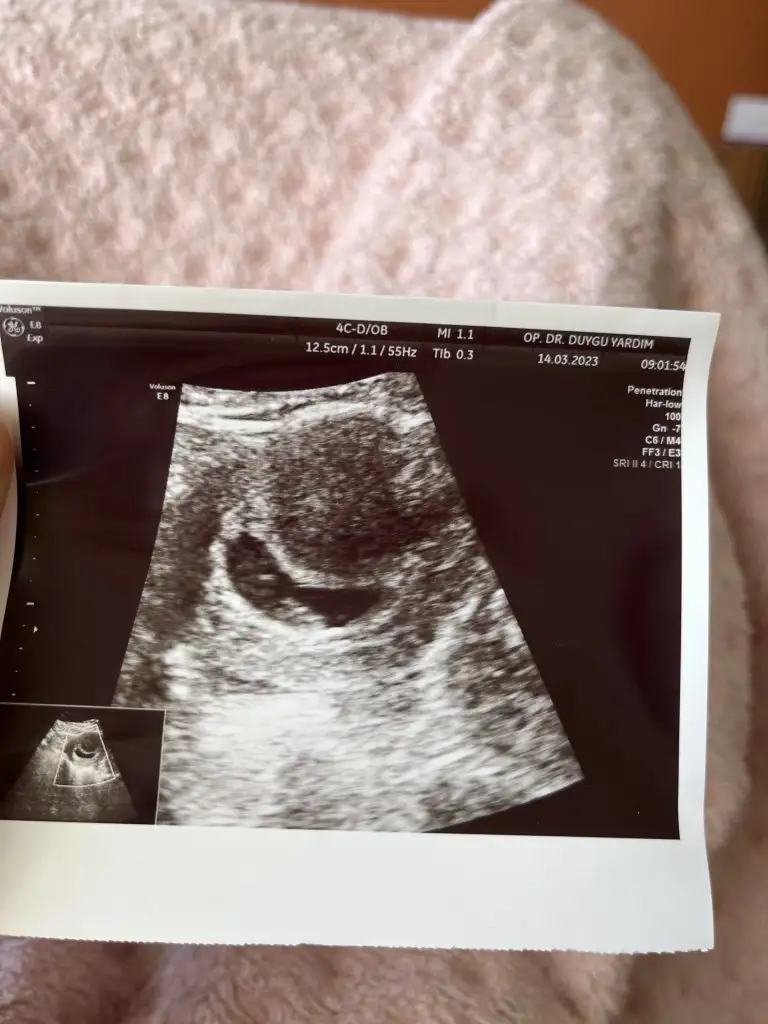

Nasıl oldun kanama azaldı mı biraz? Ultrason görüntüleri hakkında hiçbir bilgim yok..ya bir günde nasıl olabiliyor böyle bişey anlayamadım bende..çok dikkat et mutlaka..kanama alanın yok olana kadar sürekli yat..çok zor ah o yatmalar ama herşey bebek için çok zor bugünlere geldik çok kiymetliler..Bugünkü ultrason görüntüleri, kanama alanı kesenin altındaki siyah kısım sanırım doktor öyle dedi diye hatırlıyorum, tecrübeli olanlar da bi bakabilir misiniz acaba lütfen